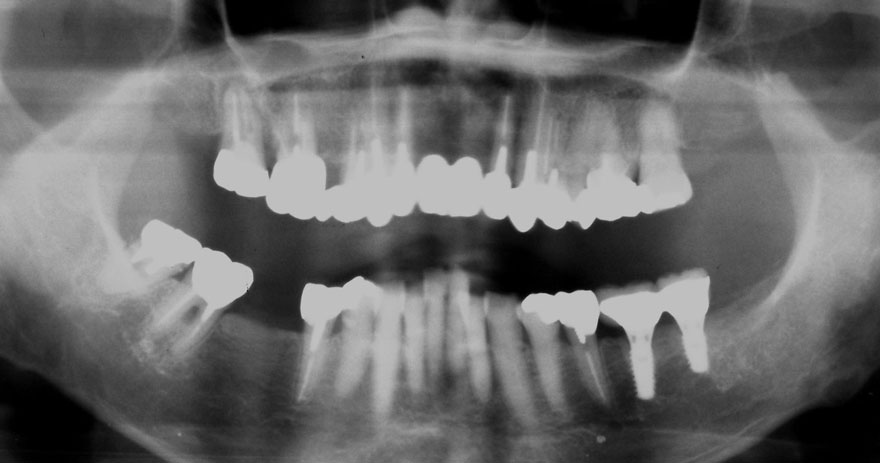

初診時 40歳 女性 平均歯槽骨喪失量:5.24mm

20年後 60歳

平均歯槽骨喪失量:5.79mm

21年間喪失量:-0.55mm

年間喪失速度:-0.027mm

(ケア頻度:1.23ヵ月ごと)